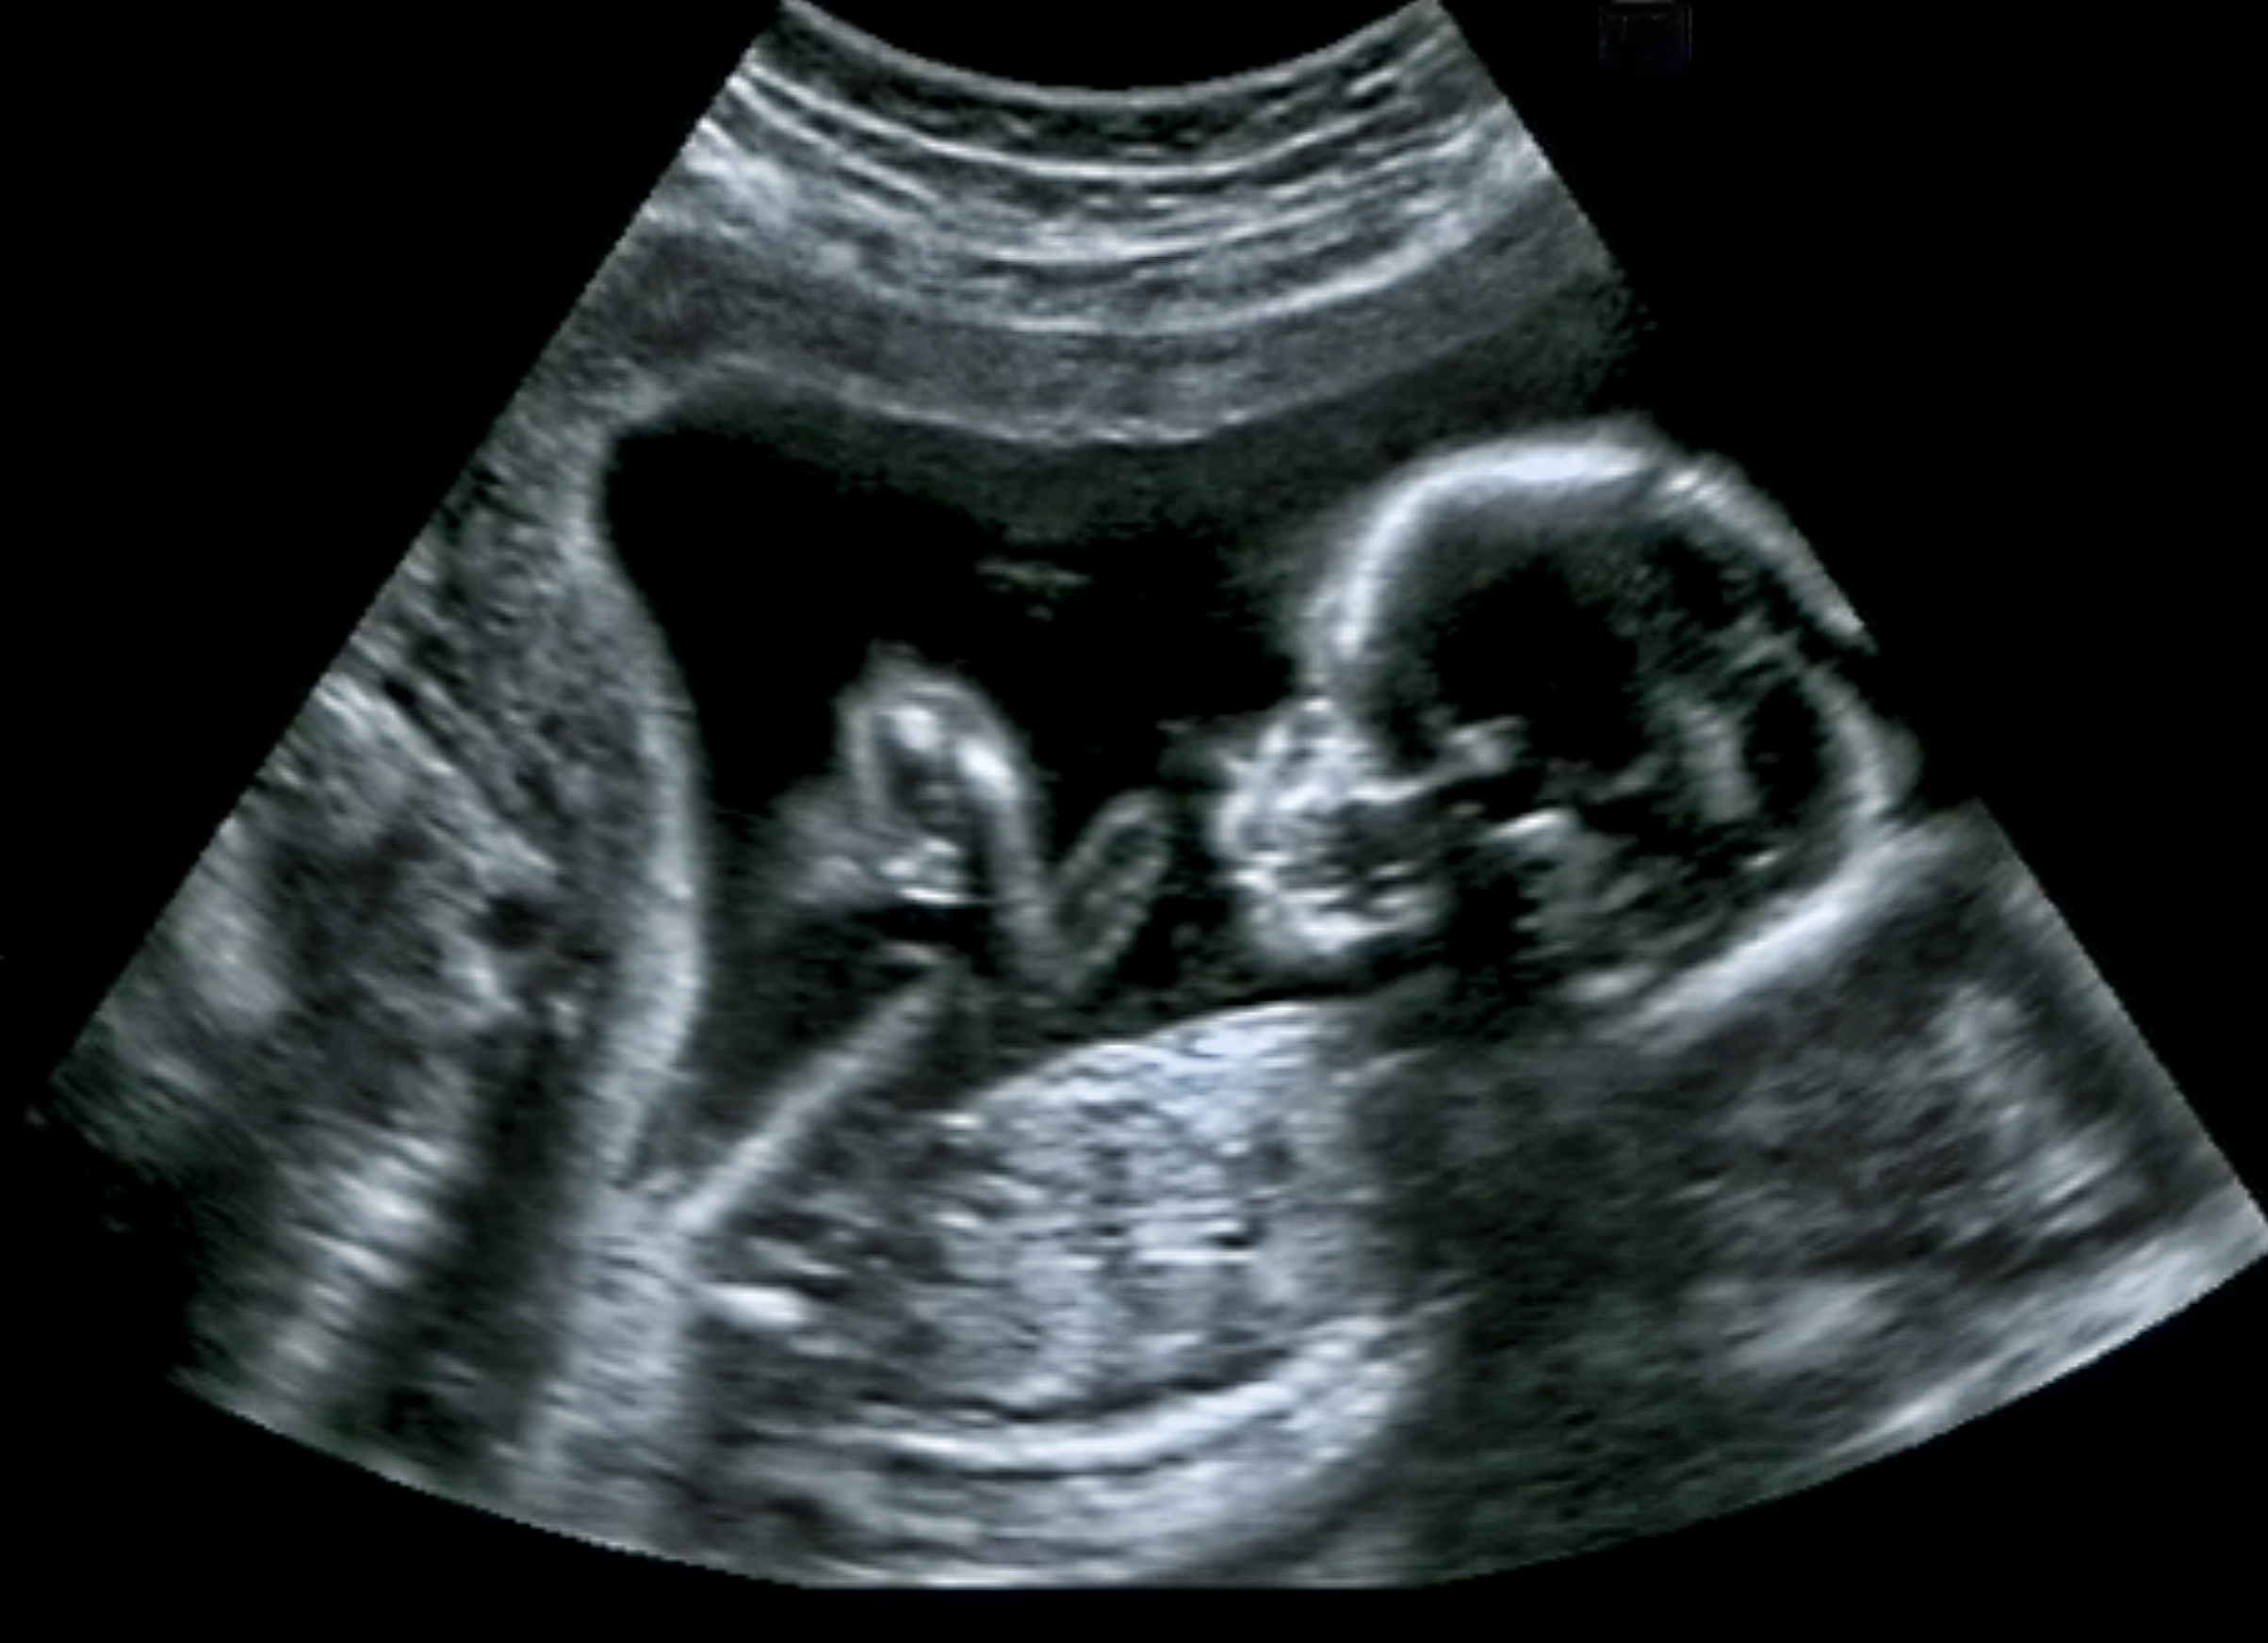

FREIBURG. Die von der Bundesregierung geplante Liberalisierung des Schwangerschaftsabbruchs darf nicht den Lebensschutz des ungeborenen Kindes gefährden. Das hat der Moraltheologe Jochen Sautermeister gefordert. Eine Regulierung der Abtreibung in einem Reproduktionsmedizin-Gesetz könnte dazu führen, dass das „gesellschaftliche Bewusstsein für ein Recht des Ungeborenen auf Leben weiter schwindet“, kritisierte der frühere Lehrstuhlinhaber für Moraltheologie an der Katholisch-Theologischen Fakultät der Universität Bonn. In einem Beitrag für die Herder Korrespondenz (November-Ausgabe) schrieb Sautermeister, der zum 1. Oktober an die Universität Freiburg gewechselt war, es sei ethisch nicht angemessen, die Regeln für eine Abtreibung allein als individuelle Anspruchsrechte der Schwangeren unter Verweis auf ihr Recht auf reproduktive Selbstbestimmung zu verankern. „Rechtliche oder moralische Lösungen greifen zu kurz, wenn sie die dem Schwangerschaftskonflikt innewohnenden Ambivalenzen vereindeutigen wollen. Das Selbstbestimmungsrecht der Frau gegen den Lebensschutz des Ungeborenen auszuspielen, führt nicht weiter.“ Beratung im Schwangerschaftskonflikt stelle keineswegs das Selbstbestimmungsrecht der Frauen infrage, sondern ermögliche vielmehr einen Raum, um zu einer verantwortlichen und gewissenhaften Entscheidung zu kommen.